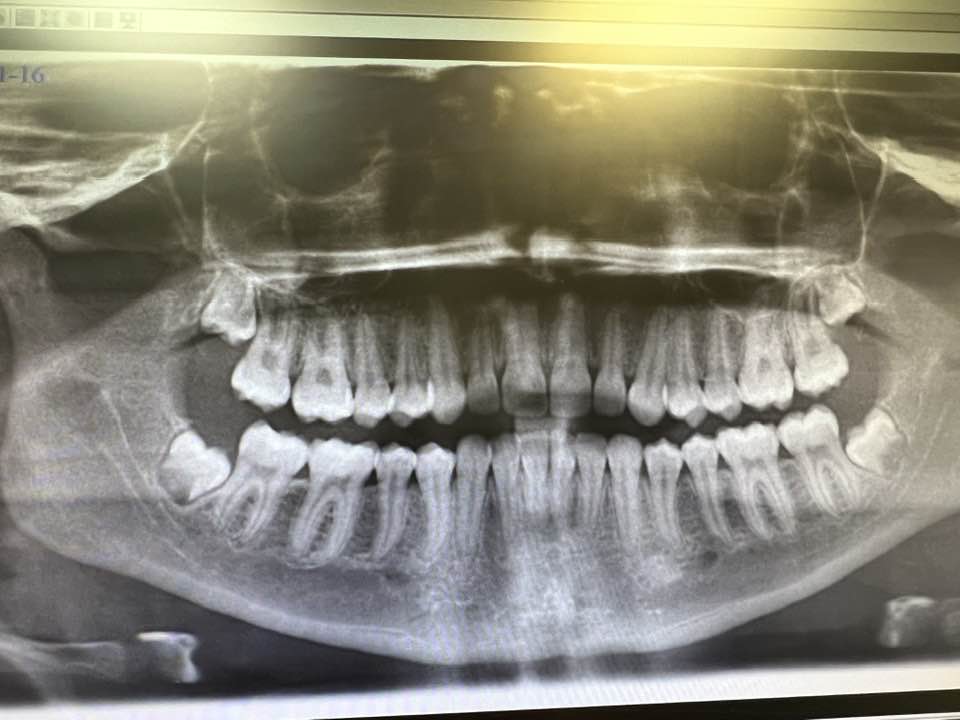

Wisdom Teeth Extraction: Wisdom teeth, or third molars, can often lead to various dental issues such as overcrowding, impaction, and infection. The team at Oral Surgery & Implant Specialists specializes in the safe and efficient removal of wisdom teeth, ensuring optimal oral health and comfort for their patients.

TMJ Surgery: Temporomandibular Joint Disorders (TMD) can significantly impact a patient’s quality of life, causing pain, discomfort, and restricted jaw movement. The experienced surgeons at Oral Surgery & Implant Specialists offer advanced surgical interventions to address TMD, providing relief and restoring optimal jaw function for their patients.